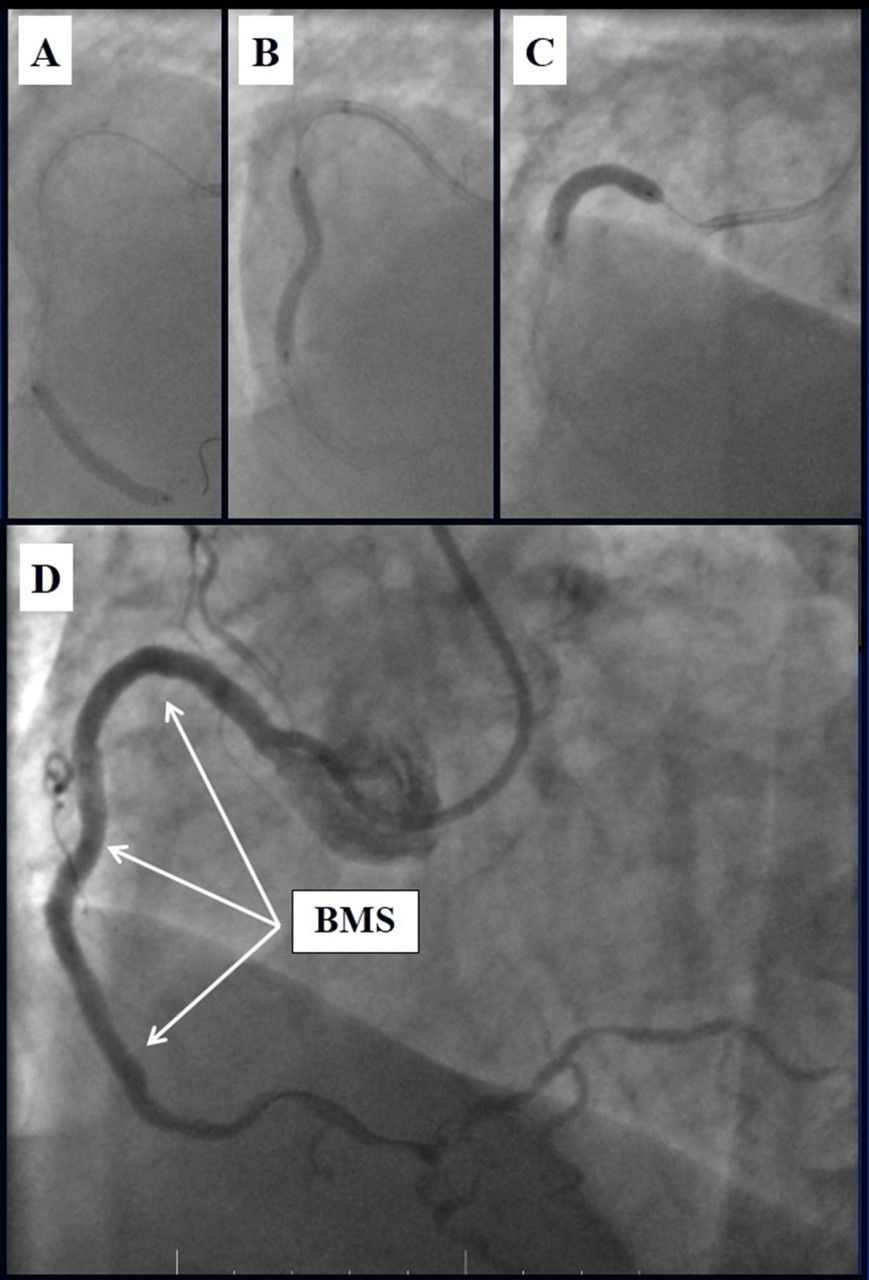

Angiography revealed rare anatomical variation LMCA quadrifurcation (Figure 1, Figure 2), 50% stenosis of the distal part of the LMCA, 40% stenosis of the ostial segment of left anterior descending (LAD) artery and diffuse prolonged 70-75-95% stenosis in mid-segment (Figure 3), 75% stenosis of the ostial segment of the circumflex (CX) artery, 75% stenosis of the ostial segment of the first marginal branch (OM1), 75-90% stenosis of the proximal segment of the intermediate artery (IMA), prolonged diffuse severe 90-95% stenosis of mid-segment of the right coronary artery (RCA) (Figure 4).

Figure 1.Quadrifurcation of the left main coronary artery

In the first stage, despite the fact that BMS is contraindicated in diabetic patients, RCA was stented with 3 bare-metal stents (BMS) (Rebel, Boston Scientific) (due to financial problems - drug-eluting stents was not covered by insurance). We used BMS to have at least temporarily patent RCA during LMCA stenting (Figure 5) (we believe that, when RCA is functional, LMCA stenting is safer). LAD was stented with 2 drug-eluting stents (Resolute Integrity, Medtronic). After the first PCI patient’s symptoms were relieved (Figure 6).

Figure 5.A, B, C - Stenting of the RCA with BMS; D - Angiography result.